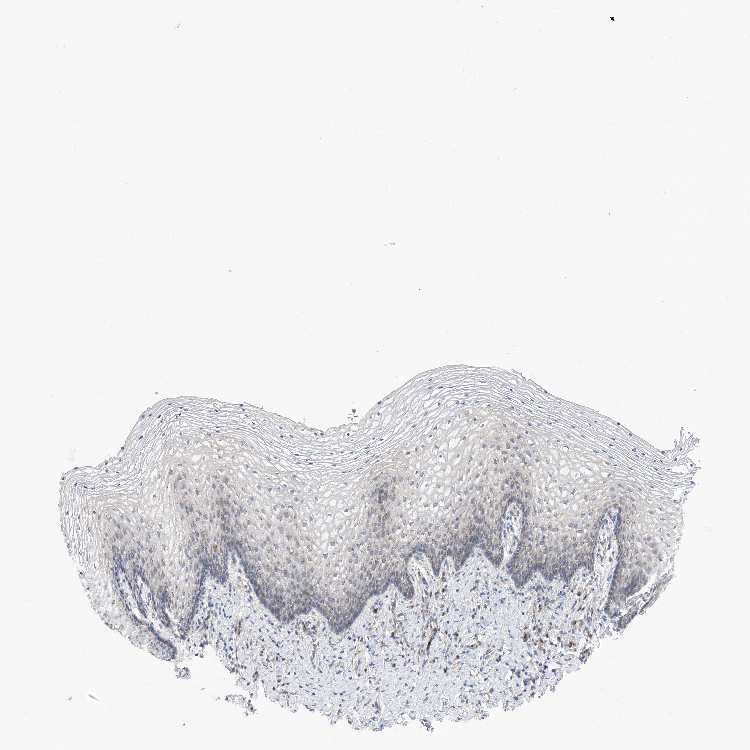

TISSUE PRIMARY DATA VAGINA Show tissue menu

VAGINA - Antibody stainingi

Antibody staining in the annotated cell types in the current human tissue is reported as not detected, low, medium, or high, based on conventional immunohistochemistry profiling in selected tissues. This score is based on the combination of the staining intensity and fraction of stained cells.

Each image is clickable and will lead to virtual microscopy that enables deeper exploration of all samples and also displays staining intensity scores, fraction scores and subcellular localization as well as patient and tissue information for each sample.

Antibody HPA030164Antibody HPA030165Antibody HPA030166

Squamous epithelial cells LowMediumMedium